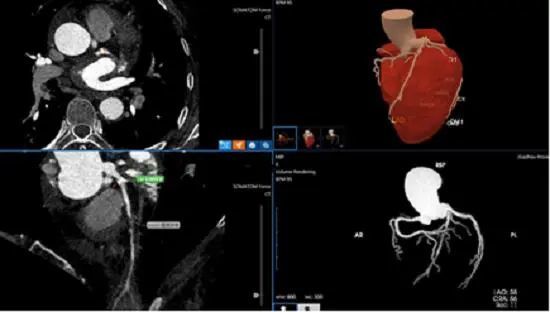

6月21日,筆者從貴州省人民醫(yī)院獲悉,該院醫(yī)學(xué)影像科診斷醫(yī)生近日運用人工智能醫(yī)療技術(shù)僅用5分鐘,就為一名左前降支重度狹窄患者作出準(zhǔn)確診斷,經(jīng)人工智能輔助診斷冠心病技術(shù)快速準(zhǔn)確診斷為冠心病。確診后,在貴州省人民醫(yī)院心內(nèi)科施行冠狀動脈介入治療后,目前該患者術(shù)后恢復(fù)良好。